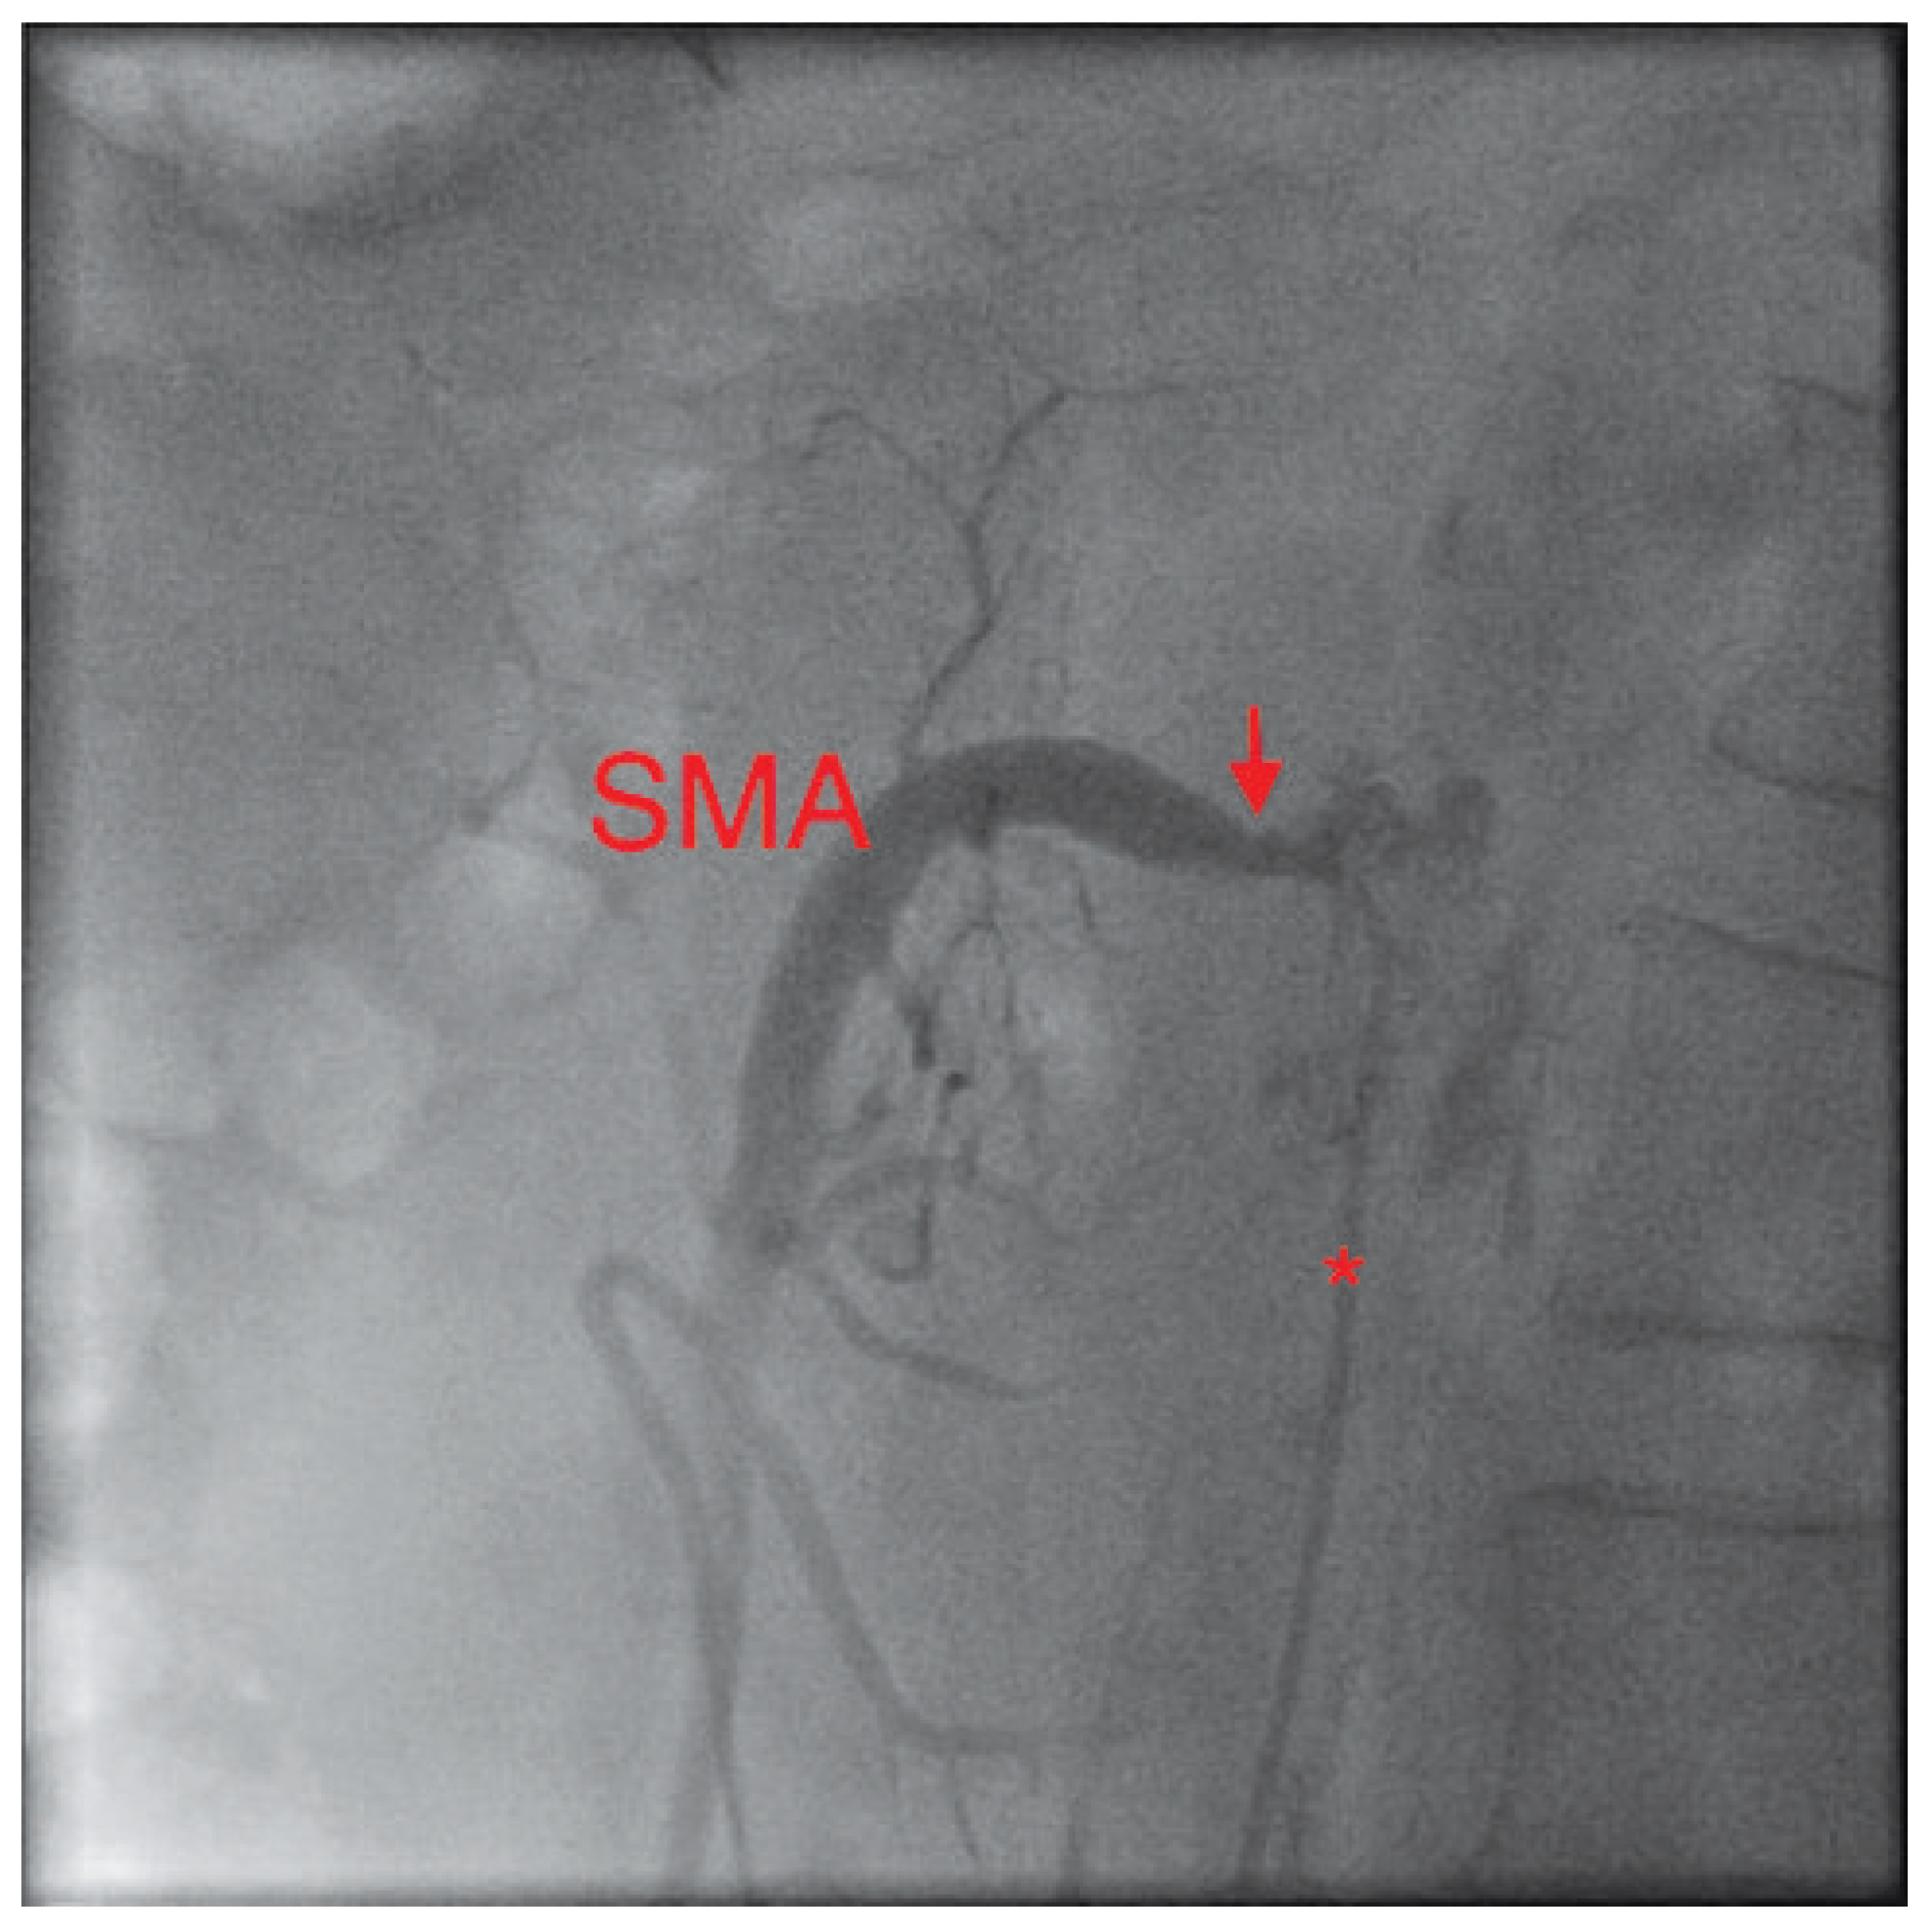

Figure 1. In this lateral view, the catheter (*) in the abdominal aorta can be seen left of the spine. Its tip lies selectively in the superior mesenteric artery (SMA). The severely narrowed neck of the SMA can be clearly seen (arrow).